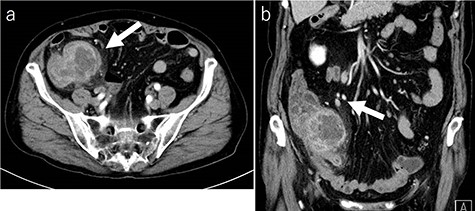

Laboratory tests revealed that her white blood cell count and carcinoembryonic antigen (CEA) levels were within normal limits (8600/μl and 2.4 ng/ml, respectively). However, C-reactive protein and carbohydrate antigen 19–9 (CA 19–9) levels were elevated (17.73 mg/dl and 87.8 U/ml, respectively). Colonoscopy showed swelling of the Bauhin valve and an elevated tumor of the terminal ileum (Fig. 1), but the biopsy specimen showed no malignancy. Abdominal contrast-enhanced CT detected a partially high-density tumor (diameter: 90 × 70 mm) in the cecum with some peripheral lymphadenopathy (Fig. 2). Magnetic resonance imaging (MRI) revealed a tumor (diameter: 60 × 40 mm) with thickening of the appendix wall near the cecum (Fig. 3). Although her pain resolved with conservative therapy, we diagnosed as suspected cecal cancer based on the imaging findings and elevated tumor marker levels.

CT findings (a: axial image in the artery phase; b: coronal image in the artery phase). Abdominal contrast-enhanced CT showing a partially high-density tumor (diameter: 90 × 70 mm) at the cecum and some peripheral lymphadenopathy (shown by arrow).